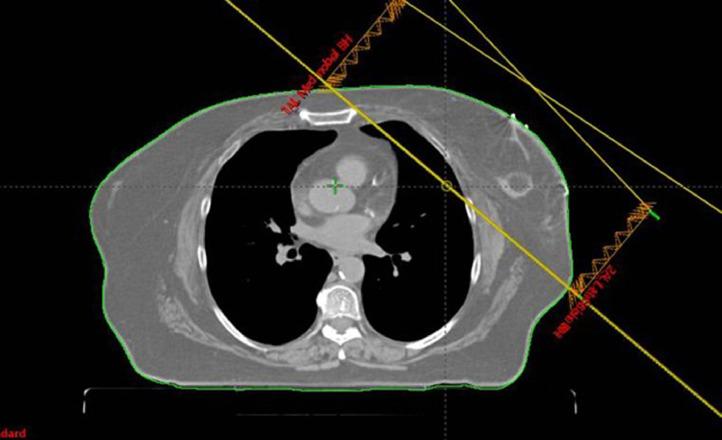

Preoperative Accelerated Hyperfractionated Whole-Breast Radiation as Treatment for Secondary Angiosarcoma of the Breast After Prior Accelerated Hypofractionated Whole-Breast Radiation Therapy: A Case Report and Review of the Literature.

Adv Radiat Oncol. 2022 Jan 19;7(4):100846. doi: 10.1016/j.adro.2021.100846. eCollection 2022 Jul-Aug.

DOI:10.1016/j.adro.2021.100846

PMID:35243183

原文链接:https://pmc.ncbi.nlm.nih.gov/articles/PMC8866668/